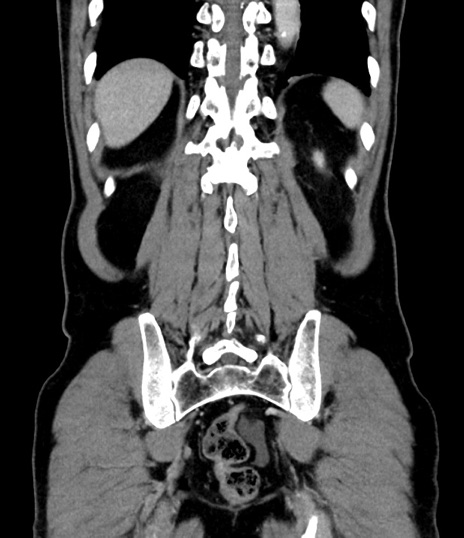

症例8(冠状断像)

【症例】 60歳代男性

【主訴】 黒色吐物

【現病歴】 4日前から嘔気自覚、2日前の朝食後にも嘔気あり、自分で手で嘔吐反射起こし嘔吐したところ血が混ざっていたため受診。

【既往歴】 5年前汎発性腹膜炎を伴う急性虫垂炎で手術、高血圧、前立腺肥大症、高脂血症

【身体所見】 腹部正中に手術癩痕あり 腹部平坦・軟圧痛なし膨満感あり

【データ】WBC 8400、CRP 4.54